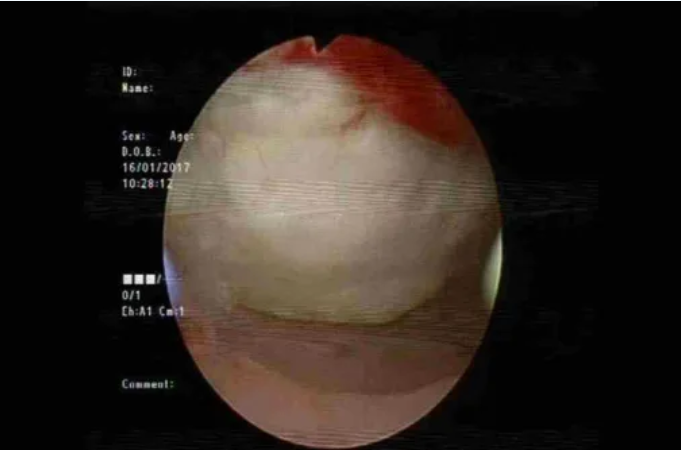

消融治疗的并发症主要包括过度治疗导致的邻近器官损伤。除影响有生育需求患者的子宫内膜或浆肌层损伤外,还可能损伤肠管(发生率1-3‰)、膀胱、皮肤及皮下组织。其中肠管损伤多为延迟性,发生于消融后5-10天。部分患者可能因血管损伤或子宫出血出现术后大出血。HIFU和微波治疗可能引发皮肤灼伤。神经损伤是HIFU特有的并发症,与靶组织后方的聚焦超声后场能量相关,这也是HIFU治疗中需采用静脉镇静镇痛的原因之一。不过,仍有少数患者出现短暂神经受累,表现为下肢感觉或运动障碍。

图:宫腔镜显示HIFU造成的子宫内膜损伤(本图由北京复兴医院马宁教授提供)